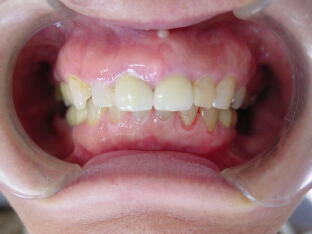

A、セラミック冠で治療した症例(上顎前歯部4本のみ治療)

切歯2本は神経のない無髄歯の為、徐々に変色をきたしていました。左右の側切歯は保険

のプラスチック前装冠です。表面がプラスチックの為時間の経過と共に材料が徐々に劣化 して変色をきたしています(下左図)。ひどい場合には削れて裏打ちの金属が見えてくる こともあります。 ![]() ![]()

歯肉状態の改善をはかり、十分なるブラッシングができるようになった後、それらをセラ

ミック冠で修復しました。